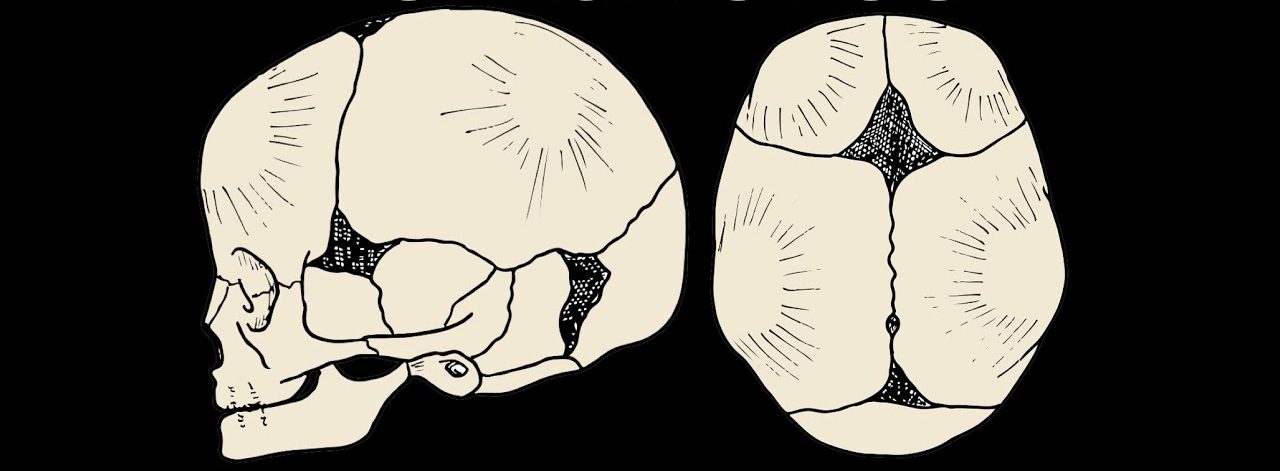

نوزائیدہ اور شیرخوار بچوں کے سر پر کچھ جگہیں نرم اورحساس ہوتی ہیں۔ انہیں تالو fontanelles کہتے ہیں۔ انہیں دیکھ کر لگتا ہے کہ چھونے سے اندر دھنس جائیں گی۔ یہ سر کی اگلی اور پچھلی جانب موجود ہوتی ہیں۔

بچوں کا جسم اور دماغ وقت کے ساتھ ساتھ نشوونما پاتے ہیں۔ اس دوران ہونے والی تبدیلیوں کو ممکن بنانے کے لئے ابتدائی طور پر ان کی ہڈیاں کمزور ہوتی ہیں۔ سر کی بات کریں تو اس کی ہڈیاں دو جگہوں سے آپس میں جڑی نہیں ہوتیں بلکہ ان کے درمیان فاصلہ ہوتا ہے۔ یہ وہ جگہیں ہیں جہاں ہڈی بننے کا عمل ادھورا ہوتا ہے۔

اسی فاصلے کے باعث نارمل زچگی کے دوران بچے کے سر کی ساخت تبدیل ہوتی ہے۔ یوں وہ اندام نہانی سے نکلنے میں کامیاب ہوجاتا ہے۔ اس کے بعد جوں جوں وہ بڑا ہوتا ہے، یہ جگہیں اس کے دماغ اور سر کے بڑھتے سائز کے لئے جگہ فراہم کرتی ہیں۔ عموماً پیدائش کے دو سے تین ماہ بعد سر کے پیچھے موجود وقفہ ہڈیوں کے جڑنے سے ختم ہوجاتا ہے۔ اگلے حصے پر موجود وقفہ 18 ماہ کے قریب ختم ہوتا ہے۔